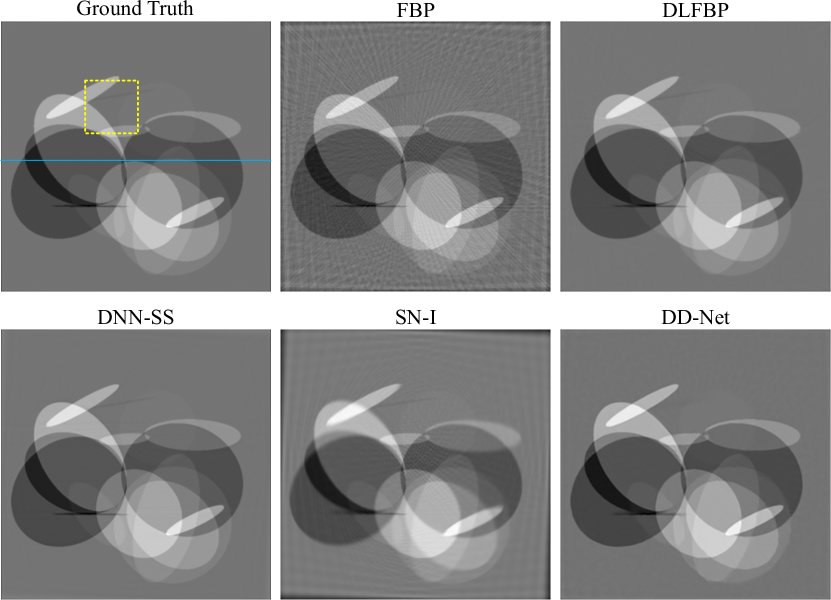

Figs.4-6 present results of one of the 100 synthetic phantoms with 120 views for testing using different methods. Same regions indicated with yellow box are enlarged for better visualization in Fig.5. The image intensity profile in same position is shown in Fig.6.

As expected, severe artifacts exist in the result using FBP, and DLFBP, DNN-SS, SN-I and DD-Net could reduce the artifacts. Though most artifacts are suppressed, there still remains some in the background using SN-I, furthermore, its central part of the image has the clearest structure and the nearer the boundary, the more blurred it is. DD-Net could also remove the artifacts satisfactorily, but the result is overly smoothed, and there is slight distortion in the edge structure. As shown in Fig.5 and Fig.6, DD-Net loses small image details and the pixel value changes gently and far from the reference value. Through visual inspection, DLFBP and DD-Net could remove the artifacts and retain small structures.

Figs.8-Fig.10 present results of one of the 100 experimental abdominal slice with 120 views for testing using different methods. Same regions indicated with yellow box are enlarged for better visualization in Fig.9. The image intensity profile in same position is shown in Fig.10.

Still, SN-I could not completely remove the artifacts, and its edge is blurred. As shown in Fig.9 and Fig.10, DLFBP, DNN-SS and DD-Net could suppress the artifacts clearly, while the result from DD-Net is overly smoothed and loses details.